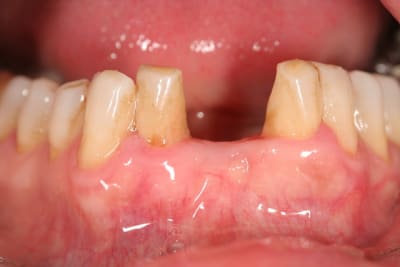

et ici ?? vous feriez quoi ?

32 et 42 pas mobiles

malheureusement, l'espace est réduit pour mettre deux implants.

comment avez vous déjà géré ce type de cas ??

le haut est déjà traité...